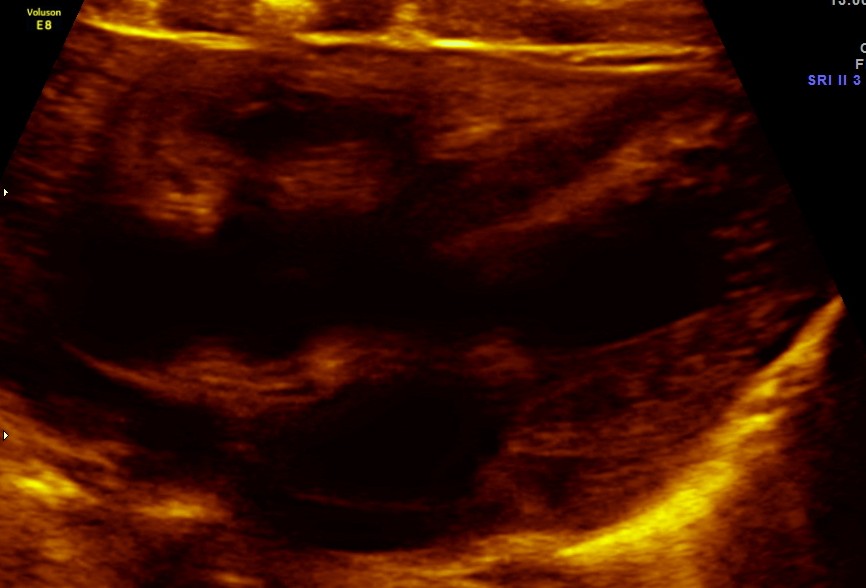

The following pictures are of the heart of the child .